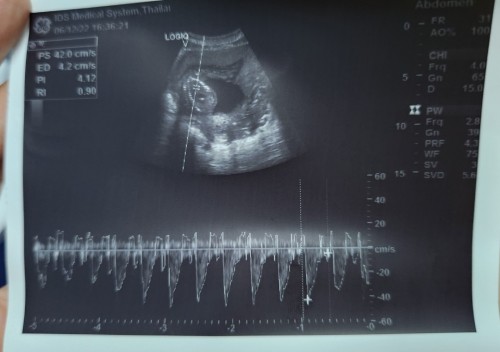

แบบนี้หัวใจน้องเต้นปกติมั้ยคะ

น้อง 16 weeks มีอาการแท้งคุกคาม

เราไปซาว 15 วีค 156 ครั้งต่อนาที หมอบอกปกติ หมอไม่บอกหรอคะแม่ ลองถามหมอก็ได้ค่ะเวลาตรวจ